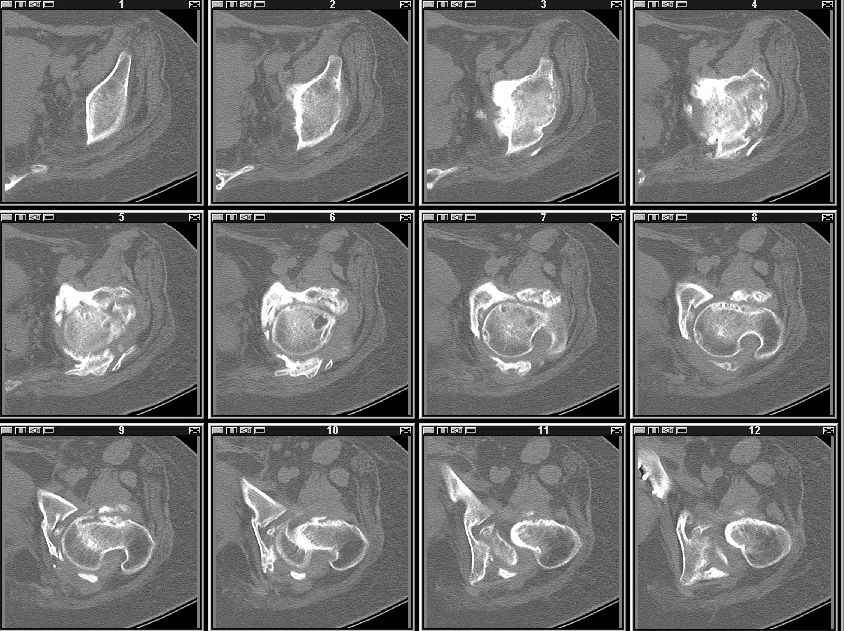

Уважаемые коллеги! Пациентка 32 года с застарелым повреждением таза, после остеосинеза лонного сочленения пластиной. Посоветуйте с выбором тактики и методик лечения.

Получила травму в феврале 2004г в г.Лобытнанги ЯНАО Тюм.обл. Через неделю после поступления выполнен остеосинтез лонного сочленения пластиной. 1,5 месяца на скелетном вытяжении. В последующем ходит при помощи костылей с нагрузкой на правую ногу. Имеется нестабильность половин таза, неправильно-консолидированный перелом левой вертлужной впадины, невропатия седалищного нерва слева. В результате невропатии седалищного нерва сформировалась эквинусная установка левой стопы,парестезии по подошвенной поверхности.

Направлена к нам для устранения патологической установки стопы и эндопротезирования левого тазобедренного сустава, также имеется миграция шурупов пластины, фиксирующей лонное сочленение.

Клинически: ходит на костылях с нагрузкой на правую ногу. Левая стопа в эквинусе. Осевая нагрузка на левую н\конечность болезненна в области левого тазобедренного сустава, при прикосновениях к подошвенной поверхности стопы у пациентки чувство зжения. В левом коленном суставе полный обьем движений, в левом тазобедренном резко ограничено отведение и ротация, укорочение левой н\конечности на 2,5 см. При полипроекционной и функциональной Р-графии выявлена нестабильность левого КПС и лонного сочленения, консолидированный в порочном положении поперечный оскольчатый перелом левой вертлужной впадины с центральным смещением головки бедра. Нами выполнена коррекция деформации левой стопы. Планируется выполнить введение 2 канюлированных илиосакральных винтов слева, реостеосинтез лонного сочленения реконструктивной пластиной, после заживления ран - тотальное эндопротезирование левого тазобедренного сустава.

На сегодняшний день надо уточнить степень сращения впадины, величину дефекта, надо делать кт шаг 2-3мм не больше. Если сращения нет - отдельная песня.